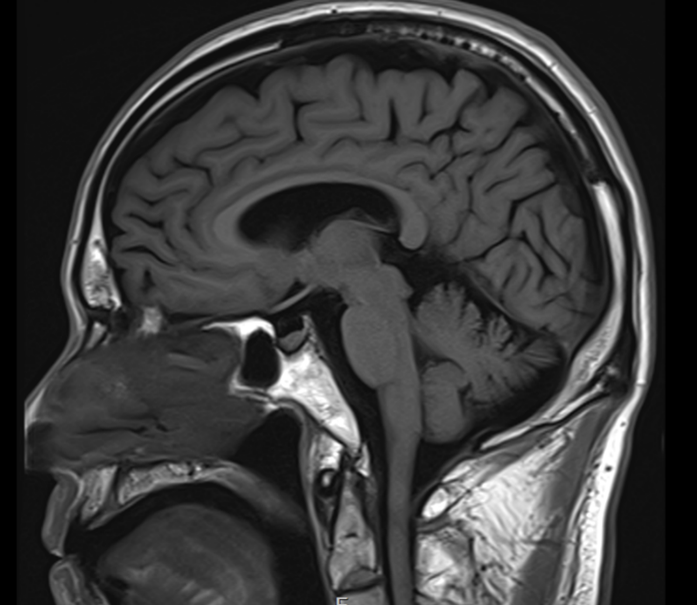

일단 가져오신 뇌 MRI 결과지를 봤는데요.

확실히 뇌졸중이나 뇌종양 같은 심각한 문제는 없었어요.

그림13.png <딱 봐도 이상한 점은 없는 정상 소견의 뇌인 게 보이죠? ^^>

이런 경우 많은 병원에서 그냥

"나이 들면 그럴 수 있어요" 하고 마무리하는 경우가 있는데...

저는 좀 더 파고들어야겠다 싶었습니다.